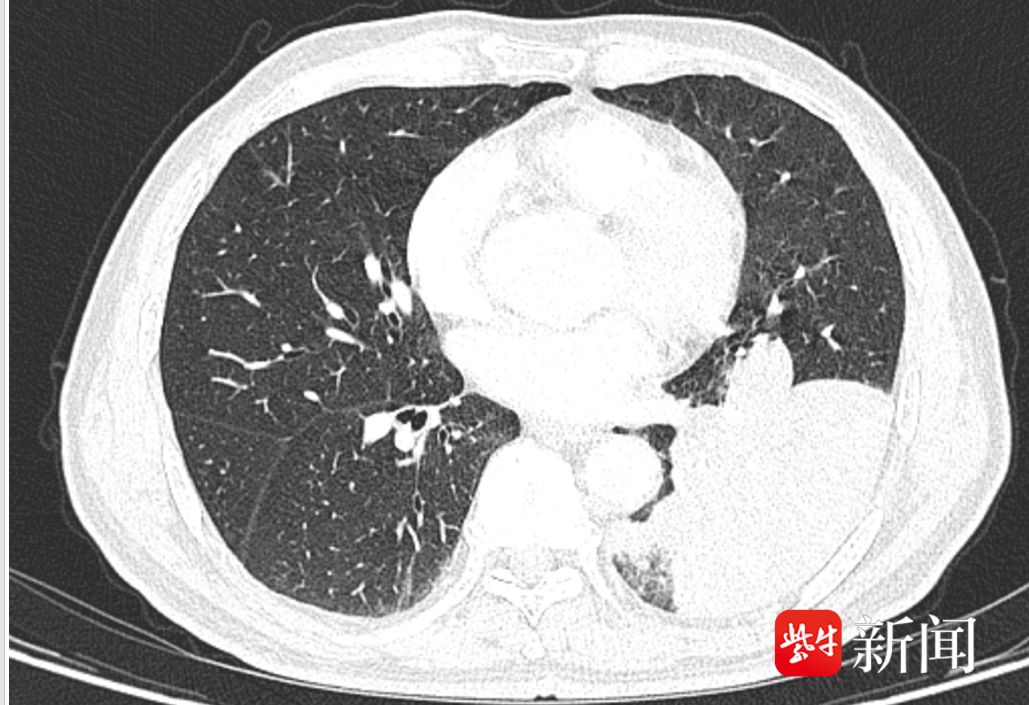

74岁的李老伯平时有进食后容易呛咳的毛病。半个月前,他在家吃鱼时被呛了一下,接着又剧烈咳嗽了一阵。因为自己有进食后容易呛咳的毛病,所以李老伯对这次呛咳并没太放在心上。然而,从那天起,李老伯的咳嗽次数明显增多,而且还伴有浓痰,虽然李老伯自己总说不碍事,但家人始终觉得不对劲,于是带着李老伯到我院河西院区呼吸与危重症医学科门诊就诊。接诊医生为李老伯安排了胸部CT检查,结果显示李老伯左肺下叶出现了一片“占位性病变”!这个病变是肿瘤?还是感染?为了明确诊断,李老伯被收治入院治疗。

入院后,河西院区呼吸与危重症医学科团队仔细研判了李老伯的病情。病区主任、医学博士杨振华敏锐捕捉到一个关键细节:李老伯既往有明确的饮食后呛咳史,且此次发病前有吃鱼后呛咳的经历。“这应该不是肺部感染或肿瘤,高度怀疑是气道异物,要对李老伯进行支气管镜检查!”